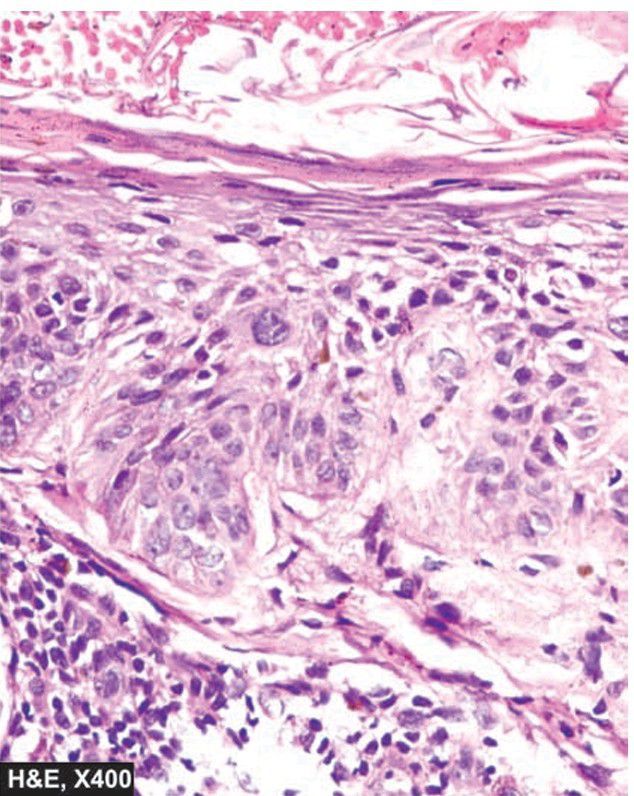

. The epidermis is thick with loss of rete ridges but the normal base to surface maturation of epidermal layers is effaced. Instead, there are bizarre atypical squamous cells but the border between the epidermis and dermis is intact i.e. the basement membrane is not breached.